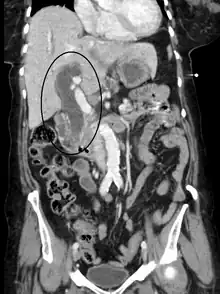

Vias biliares dilatadas por obstrução.